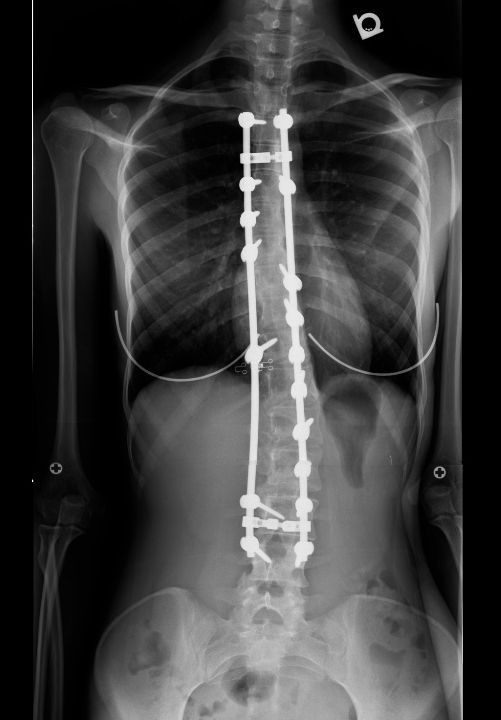

Pre-op Post-op